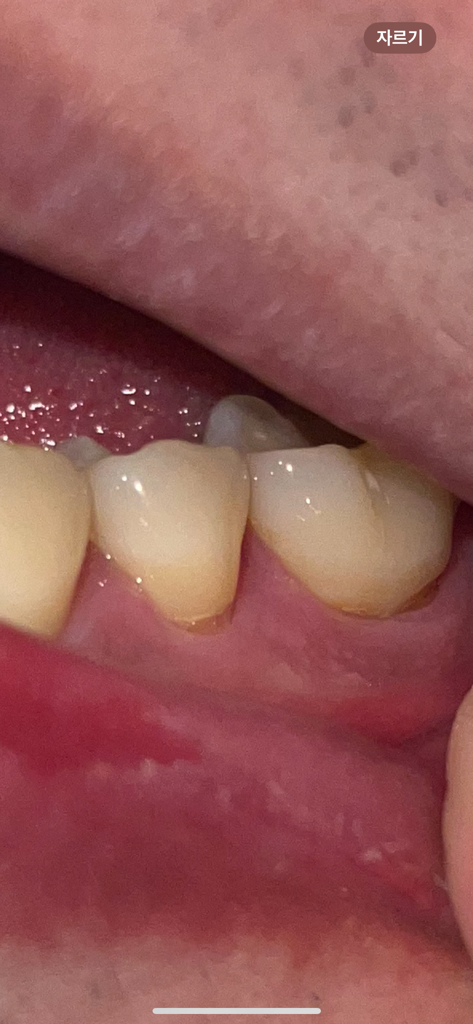

잇몸이 약간 내려가기는 했으나 심각한 정도는 아닙니다. 앞으로 관리를 잘해주시면 되겠습니다.

치경부 마모증이 시작되는거 같습니다. 시린증상이 잇다면 치료를 받으시고 괜찮으시면 양치를 너무 강하게 하지 않는게 중요합니다 .

치아의 옆 부분에 마모층이 생기게 되면 시립 증상이 있을 수 있습니다. 이런 시린 증상은 대부분 시간이 지나서 줄어들지만 증상이 지속된다면 해당 부위를 치과재료로 충전해 줄 수 있습니다. 마모가 진행되지 않도록 양치질을 할 때 너무 과도한 힘으로 치아를 솔질을 하지 않는 것이 좋습니다.

현재 치경부에 마모가 있는 것은로 보이며, 해당부위를 방치하는 경우 치아시림이 발생할수 있기에 레진으로 메꾸는 치료를 받길 권합니다.

잇몸퇴축이 다소 있긴 한데 심한편은 아닙니다 잇몸관리 꾸준히 잘해주시고 시린이 치약을 사용해보셔도 좋을 것 같습니다